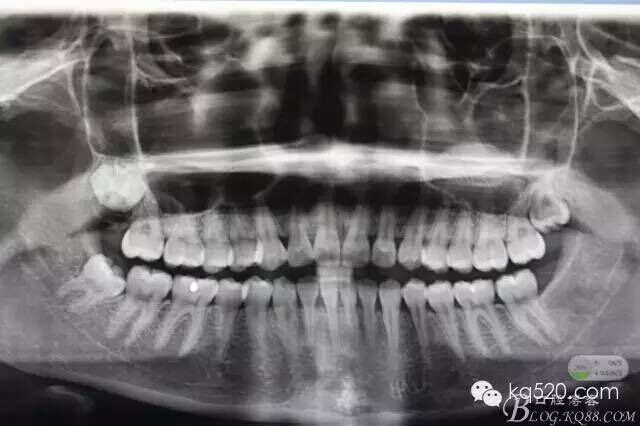

閆xx、女、19歲,主訴:右側(cè)下頜后牙不牙齦適數(shù)日。專科檢查:48未萌出、47遠(yuǎn)中有深的盲袋、可探及牙冠。牙齦輕度紅腫,x光:48近中傾斜、雙根。診斷:近中埋伏阻生。建議拔除,患者同意治療方案,簽手術(shù)知情同意書。術(shù)前設(shè)計(jì):考慮患者比較年輕,近中傾斜不大。計(jì)劃設(shè)計(jì)微切口、不分牙、微創(chuàng)拔除。

圖1.術(shù)前的x光影像檢查,48近中輕度傾斜。